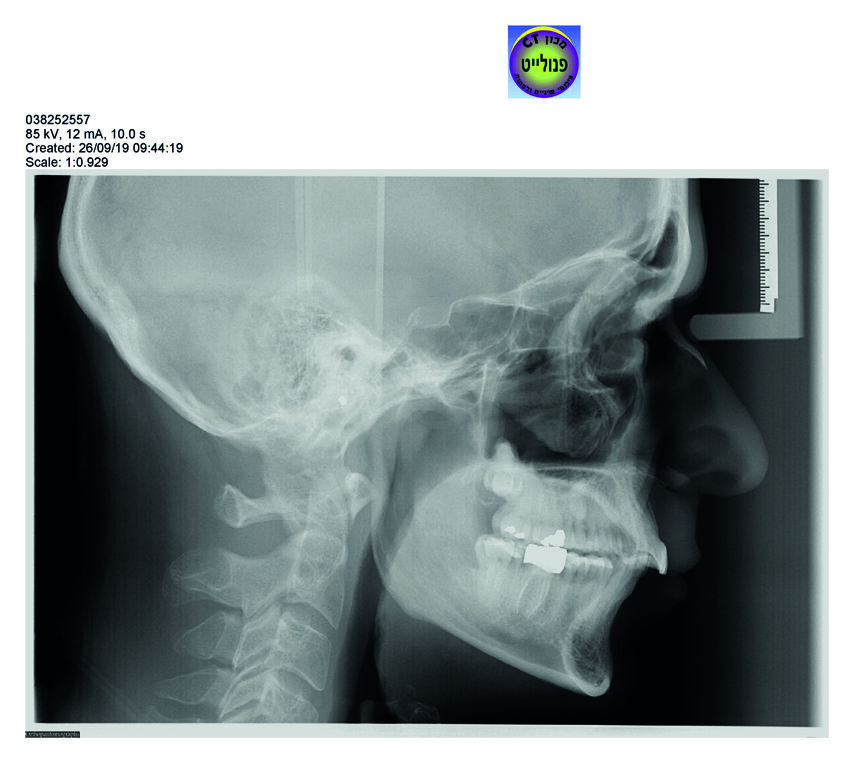

– La téléradiographie7

Le centre de radiologie de Tel Aviv utilise le système Orthocheck. Il est équipé d’un logiciel d’aide au diagnostic9.1–9.3 qui rapporte des données basées sur l’interprétation des clichés. Ainsi, pour la téléradiographie de profil, l’analyse céphalométrique faite par l’ordinateur donne les conclusions pour l’analyse orthocheck et pour l’analyse selon Ricketts.

Cette analyse est soumise à un orthodontiste qualifié. Les critiques sont les suivantes : les photographies et les radiographies sont prises en occlusion de convenance et montrent une classe I.9.4 En réalité le patient est en classe II, observation clinique confirmée tant au fauteuil que sur les photos de bouche. On note :

- Une importante version au niveau des incisives maxillaire, alors que le logiciel évoque une « upper incisor position normal » ;

- les incisives inférieures dites en position protrusive, et une classe II molaire ;

- le maxillaire supérieur en position normale et la mandibule en position rétruse avec une longueur normale, donc, une classe II squelettique.

Nous avons ici un tracé simplifié.10 Le tracé de l’incisive passe en dehors et en dessous du plancher de l’orbite. Les incisives supérieures sont dites en position normale quand le tracé de l’axe des incisives prolongé passe dans l’orbite. Dans ce cas, l’axe des incisives passe en dessous de l’orbite. On parlera donc d’une version vestibulaire. Cet élément est très simple à identifier par l’omnipraticien et permet de mettre en évidence immédiatement une version vestibulaire.

D’autre part à l’arcade inférieure, idéalement, l’axe de l’incisive fait un angle droit avec la base de la mandibule et sa position est centrée dans la symphyse mandibulaire. Chez le patient, l’incisive mandibulaire est centrée dans la symphyse, mais elle est en version vestibulaire. Nous avons une bivestibuloversion des incisives.

L’étude esthétique selon les documents fournis par le radiologue montre un profil relativement équilibré, ce qui est là aussi inexact car nous avons un profil rétrusif et une face courte